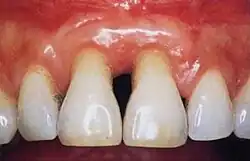

Periodontal recession on maxillary central incisors

Bone loss in periapical radiograph

The 2018 Disease Classification of Periodontal Diseases and Conditions breaks down the category of periodontitis into three forms and each of these forms are further broken down into two or more subcategories.[7]